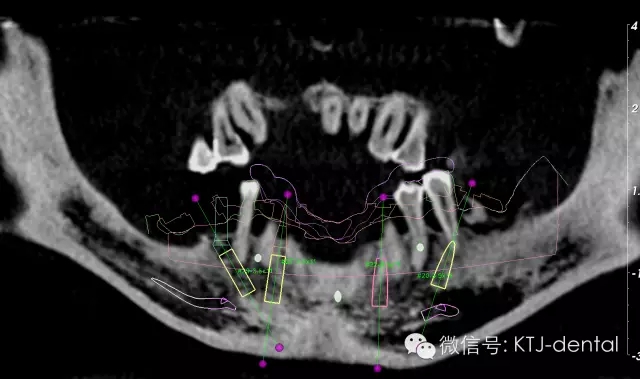

圖2 曲面斷層全景圖

圖3-4 三維立體顯示設(shè)計圖

本病案小結(jié):使用預(yù)成種植套筒冠基臺行無牙合即刻負重手術(shù)操作簡單,效果可靠,臨床應(yīng)用方便快捷。但種植體的平行度是保證此修復(fù)方式成功實施的關(guān)鍵。本病例的CAD CAM手術(shù)導(dǎo)板在應(yīng)用過程中發(fā)揮以下作用:嚴格控制種植體的平行度,避免損傷下牙槽神經(jīng)及頦神經(jīng)(無須翻瓣暴露神經(jīng)),根據(jù)種植體植入深度預(yù)選適當(dāng)?shù)幕_,根據(jù)術(shù)前打印模型預(yù)先調(diào)磨即刻負重義齒。CAD CAM手術(shù)導(dǎo)板的應(yīng)用使得手術(shù)操作有更強的預(yù)期性。在應(yīng)用技巧方面,預(yù)先保留不影響植入位點的牙齒,獲得更為精確的牙支持式的手術(shù)導(dǎo)板,減少了手術(shù)誤差。半程導(dǎo)板配套的器械盒應(yīng)該合理地與相應(yīng)種植系統(tǒng)外科器械配合使用,并根據(jù)骨的質(zhì)地采用相應(yīng)的預(yù)備方式,使得植入位點精確,并獲得良好的初期穩(wěn)定性完成下一步的即刻負重治療。